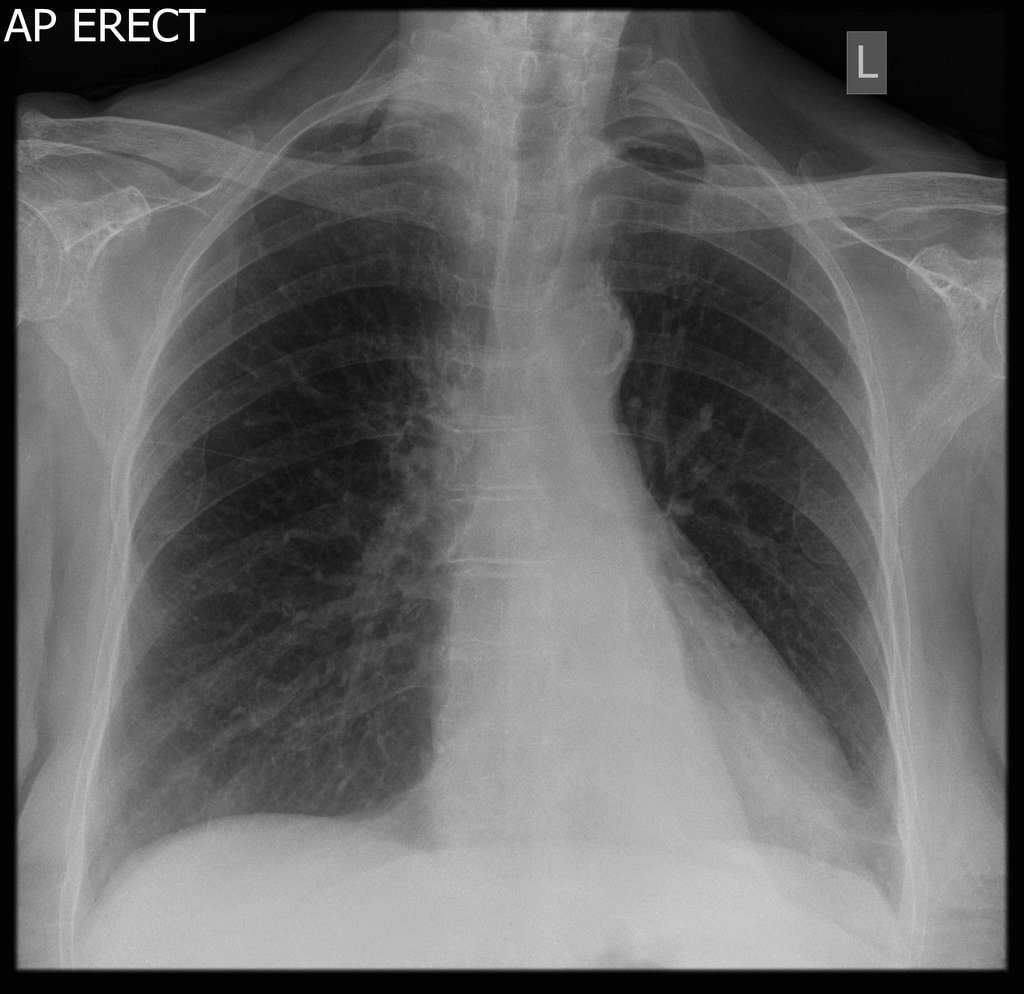

Describe the abnormality/ies

Cannonball metastases (most commonly from renal cell carcinoma)